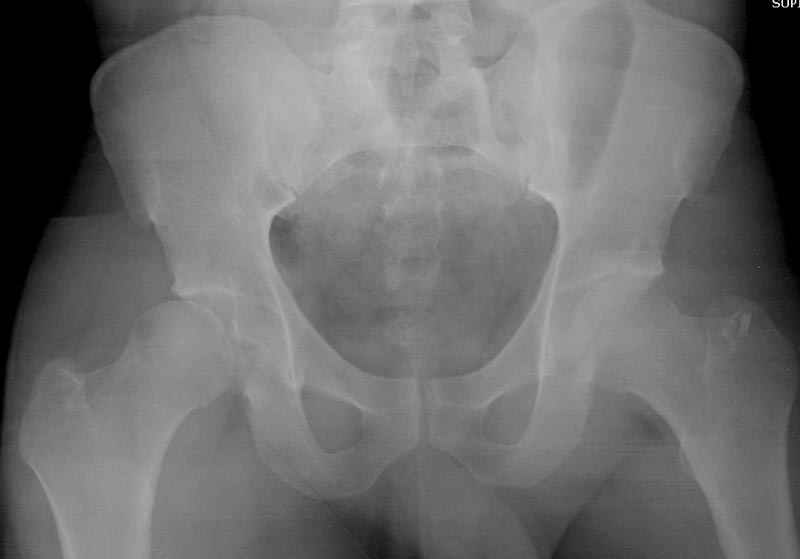

Выставлена на обсуждение (только одна проекция) рентгенограмма больного 25 лет, поступившего в приемное отделение, молодой дежурный врач сомневается в тактике лечения и спрашивает совета.

С его слов, больной стабилен,травму получил в результате автоаварии.Подскажите, что делать?Джолдас Кульджанов

5:24 Рентгенограмма таза, вызывают врача ортопеда (снимок N1), его диагноз: закрытый переломо-вывих правого тазабедренного сустава, получает добро на закрытую репозицию в приемном отделении